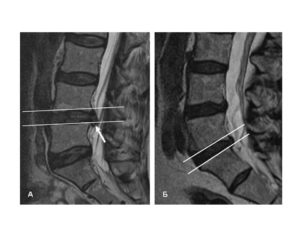

Позвоночная грыжа классифицируется зависимо от локализации, размеров, течения патологии, анатомического расположения. МРТ диагностика позволяет одновременно выявить отношение грыжи к каждому классу.

Место расположения грыж определяется латинскими буквами, обозначающими отдел позвоночника и цифрами, указывающими на порядковый номер позвонка. Например, грыжа позвоночника L5 S1 говорит о том, что поражен межпозвоночный диск между пятым поясничным и первым крестцовым позвонком. В зависимости от наличия воспаления или ущемления корешка различают радикулит и люмбоишалгию.

Первичный осмотр грамотного врача невропатолога позволяет установить уровень поражения. Для уточнения диагноза применяются современные методы диагностики — УЗИ, КТ и МРТ. До сих пор актуально рентгенографическое обследование.